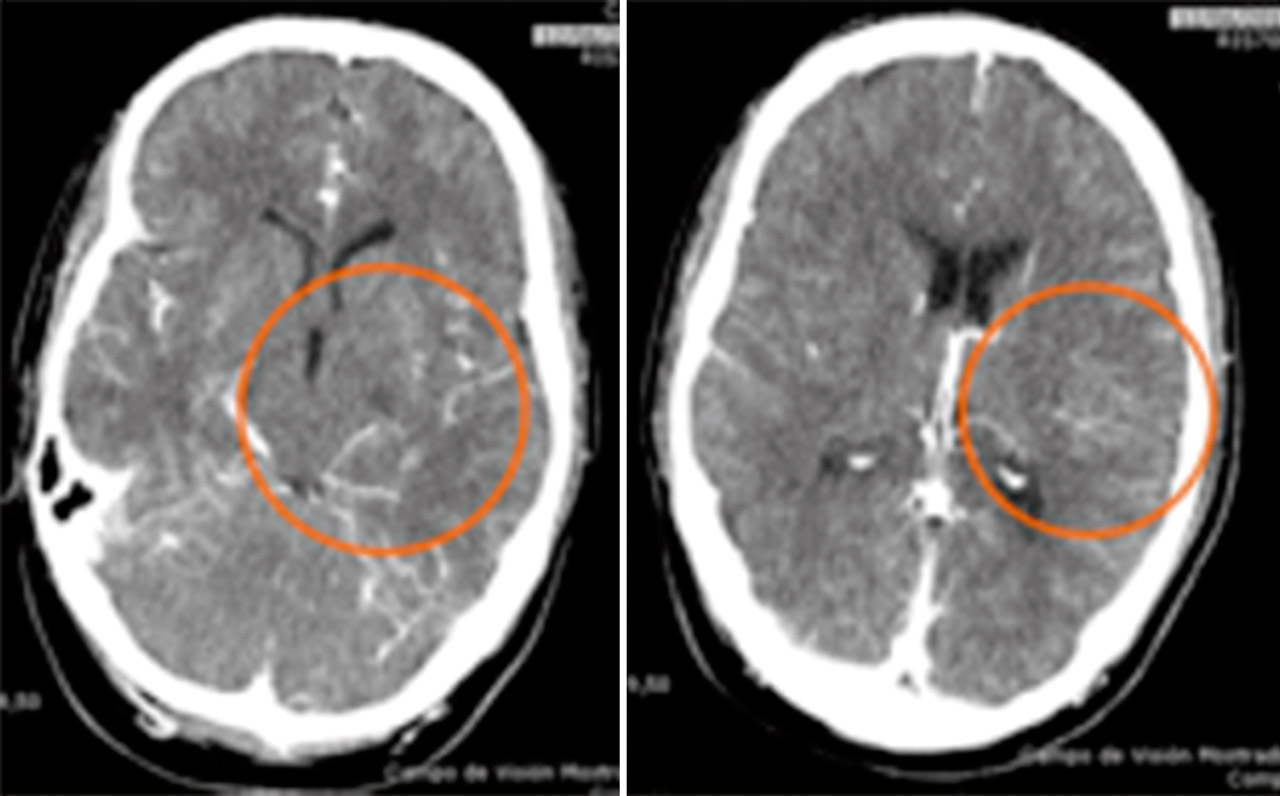

Se procedió a la desintubación, objetivando agitación y alteración para la emisión y comprensión del lenguaje. Ante la sospecha de un accidente cerebrovascular se realizó una tomografía computarizada (TC) craneal multimodal objetivando un aumento en los tiempos de tránsito medio, tiempo pico y del flujo sanguíneo, sin alteraciones en el volumen cerebral, compatibles con área de penumbra isquémica del 100%. En angio-TC, se evidenció un defecto de repleción en la arteria cerebral media izquierda, segmento M1, de 12,5 mm (Figura 6). Ante estos hallazgos, se inició el tratamiento trombolítico, 2 horas después de verle asintomático por última vez. A pesar de la mejoría progresiva, se decidió realizar una arteriografía para valorar la extensión del defecto, viendo una imagen arteriográfica compatible con oclusión crónica de M1 izquierda, sustituida por múltiples colaterales, dando el aspecto de Moyamoya (Figura 7).

Ingresó en la Unidad de Ictus 5 horas después, donde se efectuaron estudios diagnósticos. En una nueva TC multimodal persistía el defecto de repleción de M1 izquierda y múltiples vasos colaterales; diagnosticándose de síndrome de pseudo-Moyamoya.

En las pruebas de imagen realizadas, se halló obstrucción crónica en la arteria cerebral media con aumento de la circulación colateral para suplir el defecto, simulando un síndrome Moyamoya, una vasculopatía de etiología desconocida que presenta oclusión progresiva de la porción proximal de arterias cerebrales, desarrollándose vasos colaterales compensatorios(4). Dicha patología no precisa tratamiento en situación asintomática pero es necesario, en este contexto u otros, prevenir situaciones que puedan producir hipoperfusión cerebral.